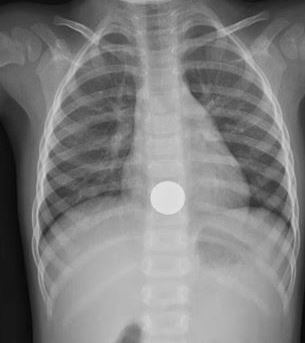

A 2 year old F presents to the ED with her parents with concern that she may have ingested a coin. Patient is well appearing with normal vital signs and exam. A CXR is obtained. What's the diagnosis? (scroll down for answer)

Answer: Esophageal Foreign Body (coin at level of GE junction)

- Coin in espophagus is en face on AP film vs. trachea en face on lateral film